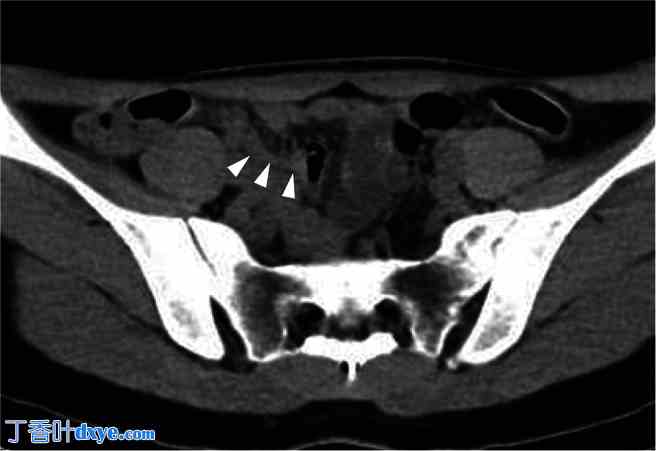

CT扫描中的阑尾扩大。

腹腔镜手术后对术前 CT 扫描进行重新评估,发现阑尾增大(箭头)。